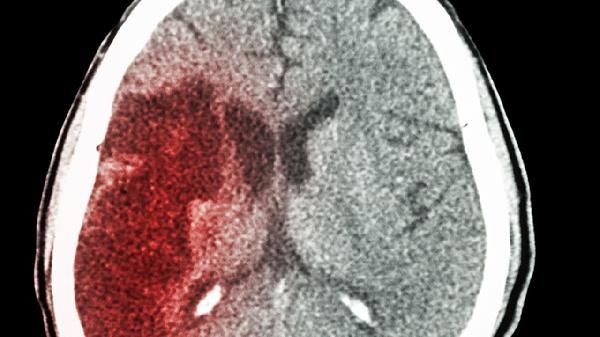

脑梗患者可遵医嘱使用阿司匹林肠溶片、硫酸氢氯吡格雷片、阿托伐他汀钙片、依达拉奉注射液、丁苯酞软胶囊等药物。脑梗用药需根据患者具体病情、合并症及个体差异制定方案,不可自行选择或调整药物。

脑梗患者除规范用药外,需长期控制血压、血糖和血脂水平,每日监测生命体征。饮食应低盐低脂,适量增加深海鱼类和坚果摄入。康复期在医生指导下进行肢体功能训练和语言康复,避免情绪激动和过度劳累。定期复查头颅影像学与血液指标,出现头痛呕吐或肢体无力加重时立即就医。